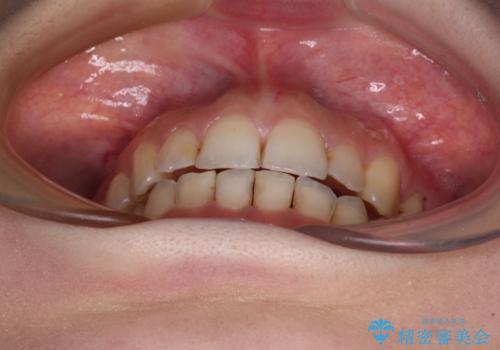

顕著な八重歯をインビザラインで治せるところまで改善

- 顕著な八重歯など、上下前歯のデコボコとスペースを気にして来院された患者様です。

補助装置だけでなく、部分的にワイヤー矯正も使用しましたが、上下のスペースは改善しきれず、側切歯(前から2番目の歯)や顕著な八重歯は、インビザラインで治療するには限界があることがよく分かりました。

より良い仕上がりを希望される場合には、ワイヤー装置による矯正治療がお勧めとなります。